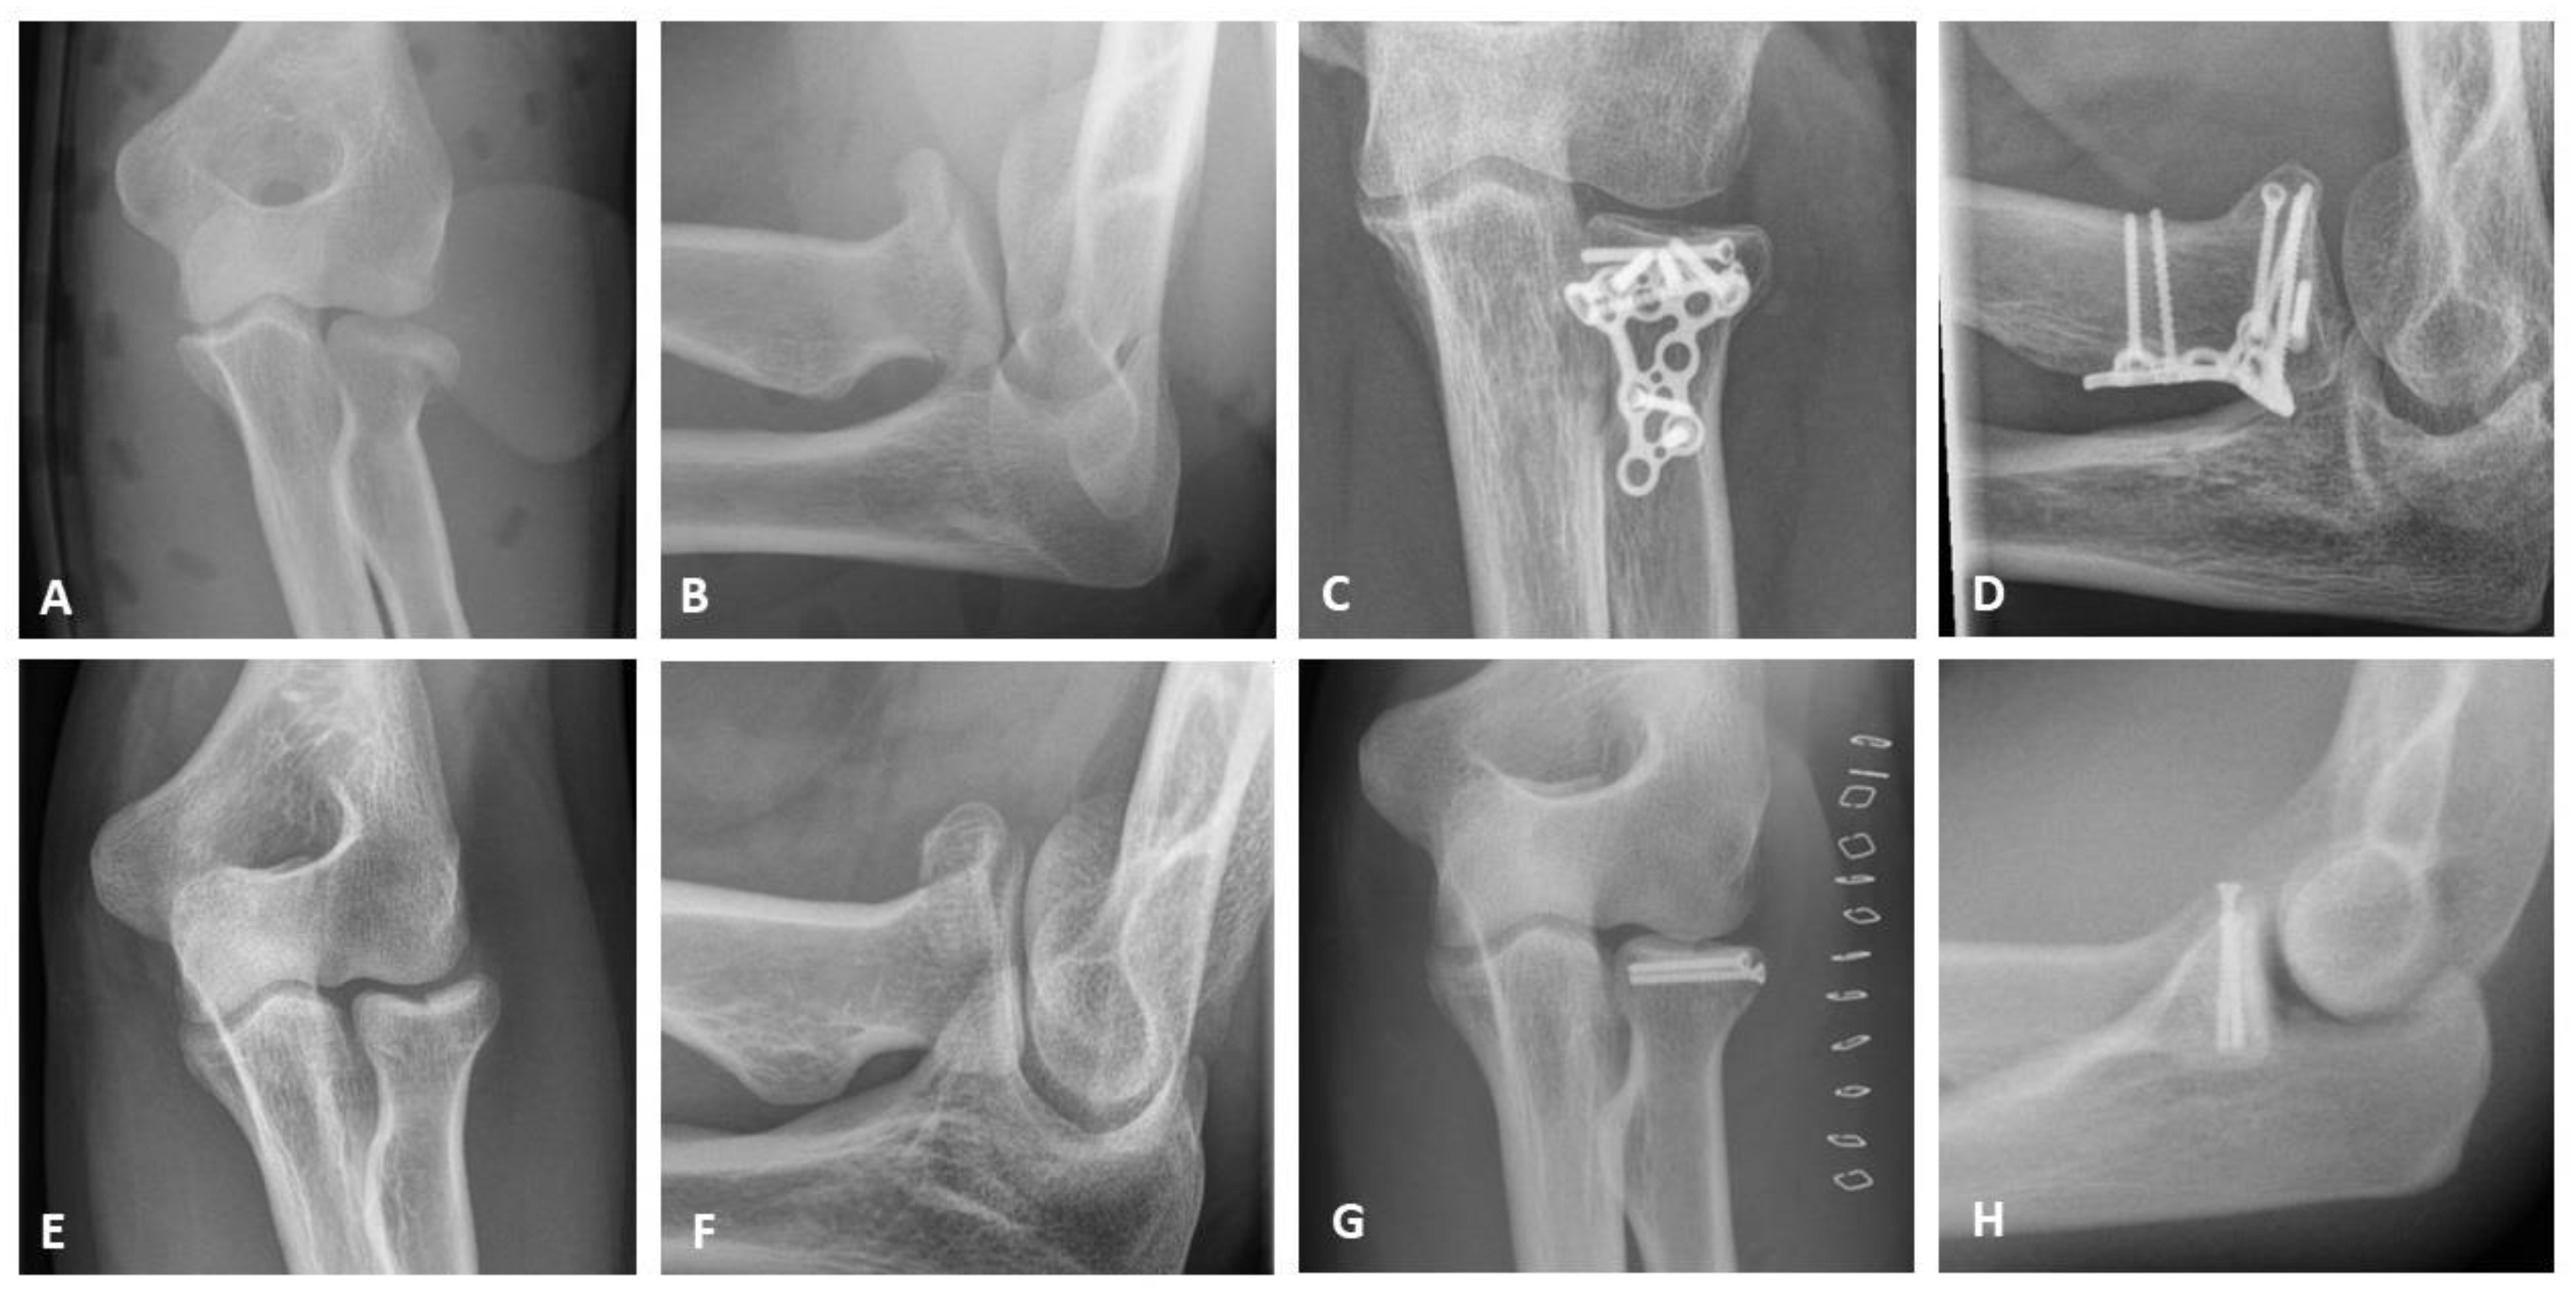

All patients underwent surgery via a lateral approach modified according to Kaplan [14]. The type of treatment was based on the instability and complexity of the fractures according to the Hotchkiss modification of the Mason classification. Simple 2-part fractures were stabilized using 2 mm lag screws (Medartis AG, Basel, Switzerland), whereas multi-fragmentary fractures were treated with 2.4 mm LCP radial head plates (DePuy Synthes GmbH, Oberdorf, Switzerland) as well as with 2.0 mm TriLock Radial Head Plates (Medartis AG, Basel, Switzerland). In case of irreparable fractures, radial head arthroplasty (RHA) was performed (MoPyC, Tornier SAS, Montbonnot Saint Martin, France). Figure 1 shows typical cases with pre- and postoperative x-rays of a mason type II fracture treated with screw osteosynthesis and a mason type III fracture treated with plate osteosynthesis.

Figure 1.

X-ray diagnostics; (A,B) Mason type II fracture in AP and lateral oblique view; (C,D) Mason type III fracture postoperatively after plate osteosynthesis in AP and lateral oblique view; (E,F) Mason type II fracture in AP and lateral oblique view; (G,H) Mason type II fracture postoperatively after screw osteosynthesis in AP and lateral view.